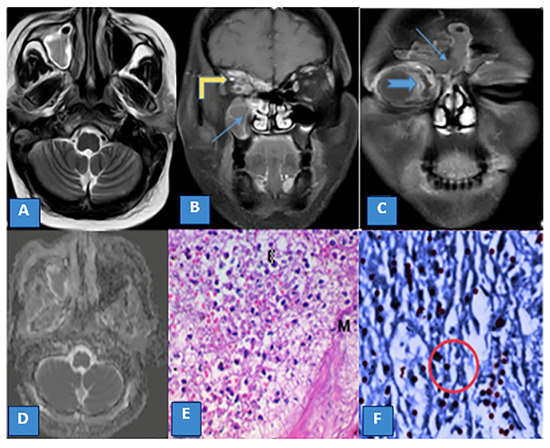

3.3. MRI Findings and Signal Characteristics

3.4. Extrasinus Extension

3.5. Histopathological Findings